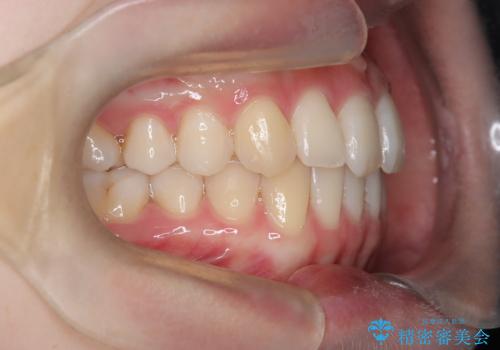

【インビザライン】 前歯の反対咬合を治したい

左下5番は先天性欠損のため乳歯は抜歯しインプラントにて欠損補綴しています。